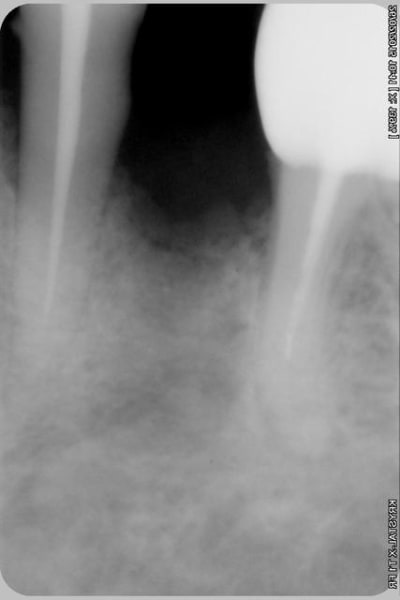

alors là pas du tout, le patient vient me voir pour des implants, donc je fais une étude du cas absence des molaires supérieures, couronnes mandibulaires très ancienne 45 racine cassée, 44 dévitalisée mais passablement déchaussée, donc avulsion de 45 et pose d'un implant avant de refaire les couronnes 46/47 et l'ensemble.

Échec implantaire, et oui ça arrive, même dans un cas paraissant simple.

Oui, un Px, le premier était un Reg.

l'os était tendre, ce qui explique le choix du Px